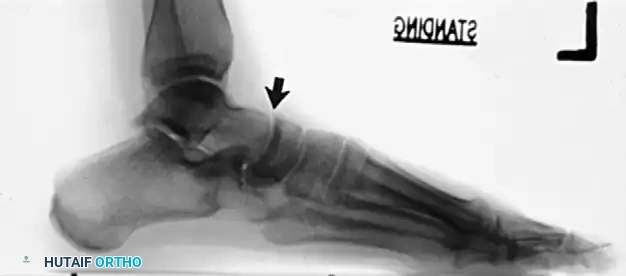

The Role of the Evans Procedure

In these advanced cases, isolated soft tissue advancement is doomed to fail. The deformity requires a combination of advancing the tendon, excising the extended corner or accessory navicular on the medial side, and lengthening the lateral column of the foot with a bicortical bone graft (Evans procedure).

The Evans anterior calcaneal osteotomy helps restore and stabilize the longitudinal arch by elongating the lateral column of the foot, thereby reducing the talonavicular joint congruously.

- The graft is usually 8 to 10 mm wide and is placed 1.5 cm proximal to the calcaneocuboid articulation.

- It is internally fixed with a single 3/32-inch Steinmann pin driven from the fourth intermetatarsal space, distal to proximal, crossing the calcaneocuboid articulation, and cut beneath the skin.